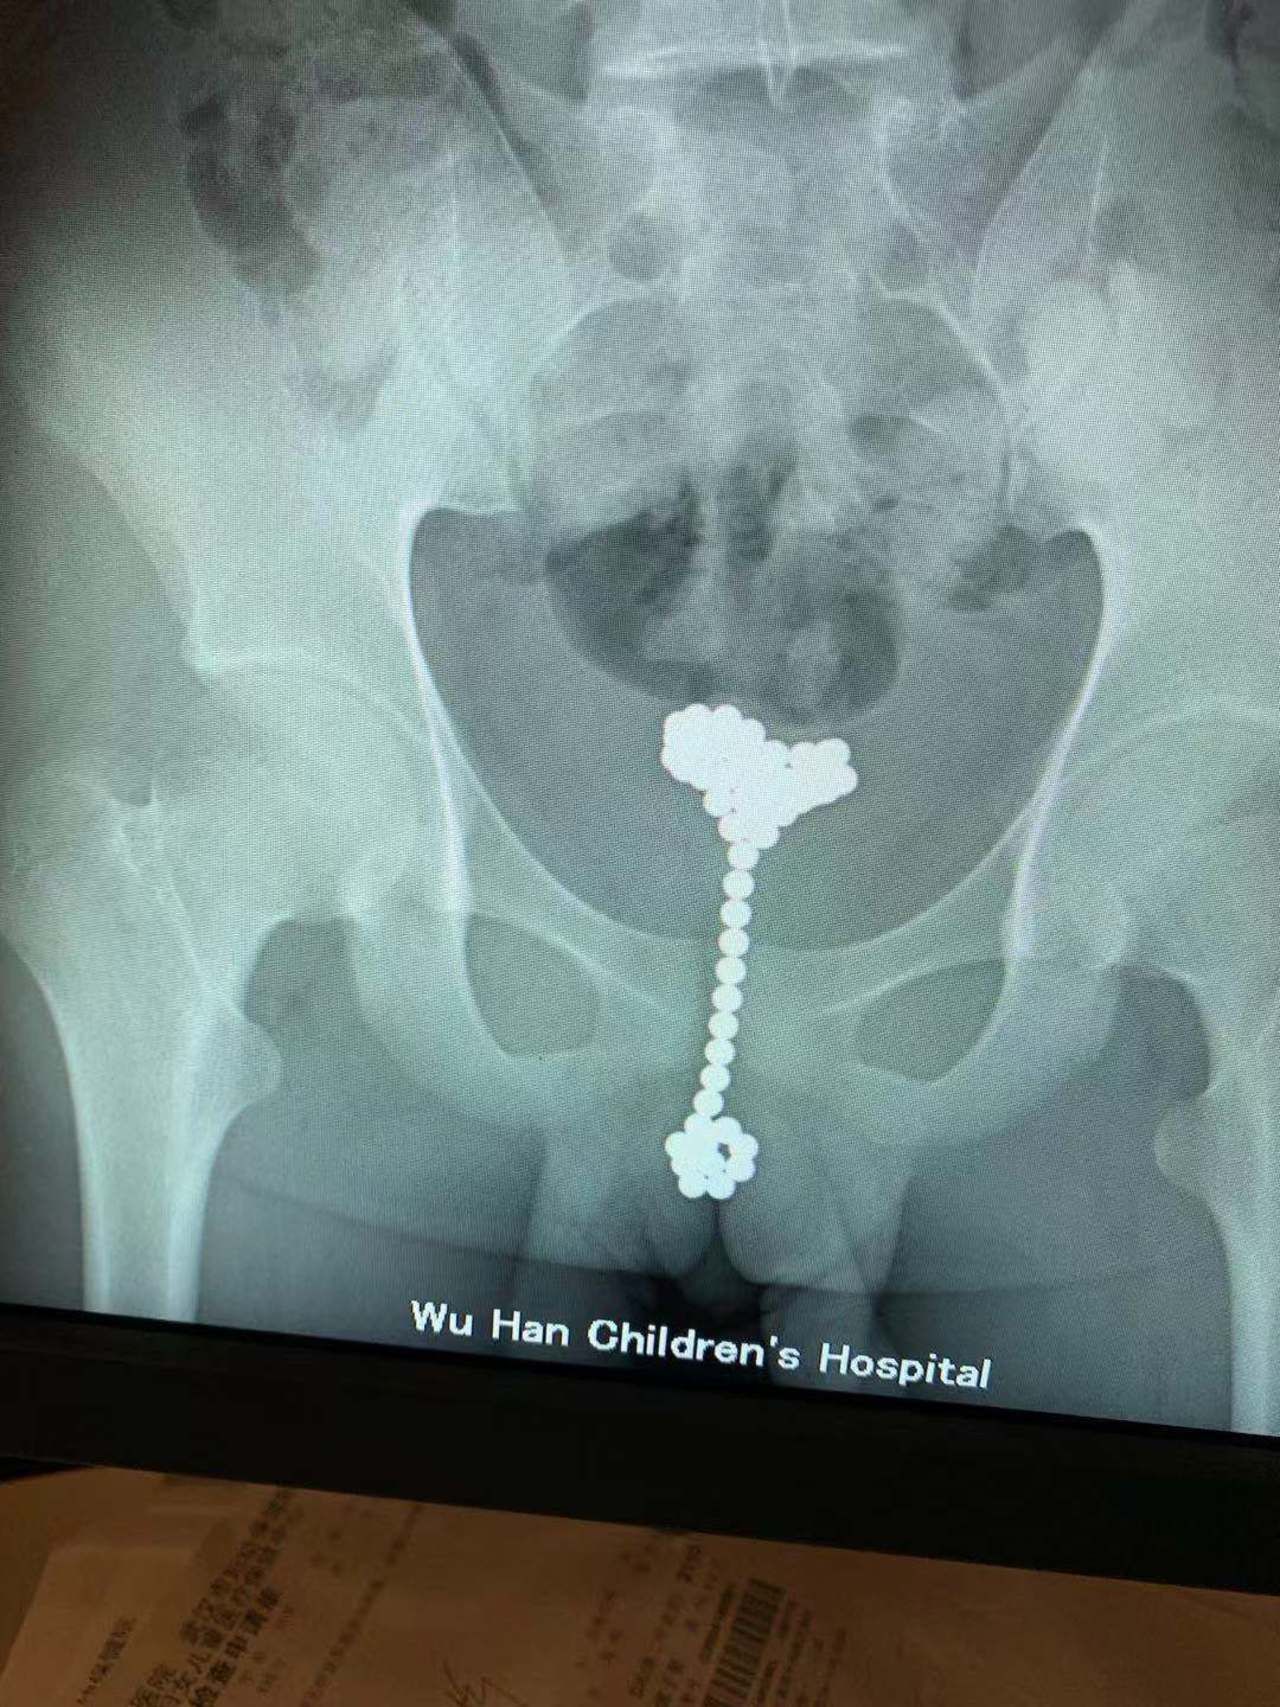

无独有偶,就在上周,还有一名13岁的少年李辰(化名),因为“肚子痛”就诊,被收治进了普外科。医生本以为是吞了异物,但该科急诊医生李欢一看片子,发现有一串金属物竟在膀胱内。

李欢特意将李辰带到单独的房间,安慰他不要害怕,劝他说出实情,医生才能帮助他。见爸妈不在,李辰这才不好意思地承认,自己是为了“探索人体”,一时好奇才将珠子塞进去的,已经过去两个多月了。李辰随后被转到泌尿外科,王军主任手术取出了31颗巴克球。